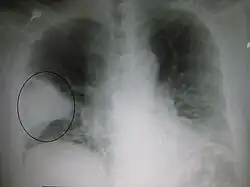

Cavities

A cavity is a walled hollow structure within the lungs. Diagnosis is aided by noting:

- wall thickness

- wall outline

- changes in the surrounding lung

The causes include:

- cancer

- infarct (usually from a pulmonary embolus)

- infection: e.g., Staphylococcus aureus, tuberculosis, Gram negative bacteria (especially Klebsiella pneumoniae), anaerobic bacteria, and fungus

- Granulomatosis with polyangiitis